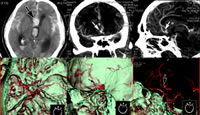

大脑前交通支小动脉瘤破裂继发蛛网膜下腔出血

患者男,58岁,突发头痛继而意识障碍3小时。

图1 CT平扫,示蛛网膜下腔出血,半球间裂额部,双侧侧裂呈高密度改变,其中透明隔间腔明显增宽(箭号)。部分血液进入脑室。

图2、3 CT血管造影经前交通支水平冠状厚层(10 mm)最大密度投影(slab MIP,图2)与正中矢状面厚层(10 mm)MIP(图3),示前交通支小囊状动脉瘤(箭号),基底较宽。半球间裂内出血仍隐约可见(星号)。

图4、5 CT血管成像,容积再现(VR),上面观(图4),侧面观(图5),示大脑前动脉前交通支小动脉瘤(箭号)。

图6 去部分颅骨后的VR图像,箭号示小动脉瘤。, http://www.100md.com